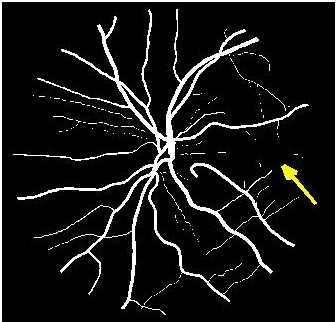

Results of fold cross validation for are presented in Table 1. Due to space constraints only SSIM values are shown for . For , performance difference of all methods is small but becomes more pronounced for higher . gives the best results for all , and the improvement over competing methods is significant as is evident from the values of Wilcoxon signed-rank tests. Figure 3 shows results of the top methods (due to space constraints) for . shows the best performance as is evident from the SR image in Fig. 3 (b) where one of the minor retinal branches (indicated by yellow arrow) is clearly visible. On the other hand the SR image by (Fig. 3 (c)) is blurry and does not clearly show this retinal branch. Other methods perform much worse, with significant blur visible for the main branches as well. Clearly, gives the closest reconstruction to the HR image of Fig. 3 (a).

![]() |

| (a) | (b) | (c) | (d) |